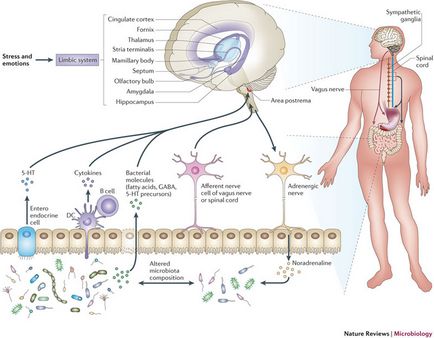

A stressz, az érzelmek, csökkenő és emelkedő agy kommunikáció és a belek. (Nature Microbiology®)

M. Gershon úgy véli, hogy van egy erős kapcsolatot a vastagbél és a pszichére, mert a nagy mennyiségű információ a környezetből származik az emésztőrendszeren keresztül. „Ne felejtsük el, a belsejét a belek valójában külső, hogy a test,” mondja. Így vagyunk képesek érzékelni veszély szem, hallani fülét, és elismerik, hogy az emésztőrendszerben. P. Pasriksha. A Johns Hopkins fej Neyrogastroenterologii Központ Baltimore emlékeztetnek: nincs bél nem rendelkezik az energia az élet fenntartásához.

„A vitalitás és biztonságos működéséhez elengedhetetlen, így az agynak szüksége van a közvetlen és szoros kapcsolatban áll a bélben,” mondja.

Kitérünk a döntéshozatalban. A „bél ösztön” vagy „gut reakció” már jól ismert, de valójában érzés borzongott eredményeképpen jön létre a jeleket az agy - a reakció küzdj vagy menekülj. Merült fel ugyanakkor a szorongás vagy izgalom valószínűleg befolyásolja a döntést, hogy leugrik egy hídról egy gumikötél most, vagy elhalasztja a kísérlet egy másik alkalommal, de az ötlet, hogy a második agy egyértelműen befolyásolja a választás nem teljes megerősítést. Tudatalatti „bél ösztön” határozottan részt vesz a működését a gyomor-bél idegrendszer, de valójában a fenyegetés értékeli és elismeri az agyban található a fejét. És a tudat, érvelés, még Gershon elismeri második agy nem képes ezeket a funkciókat. „A vallás, a költészet, a filozófia, a politika - mindez a joghatóság, az agy,” mondja.

Az egyre világosabb, hogy az idegrendszer a bél felelős nemcsak az emésztést, részben a fejlődés tanulmányok, amelyek megerősítik, hogy a második agy is lényeges, hogy széles körű agyi betegségek. A Parkinson-kór, például motor merevsége, gipomimiya, károsodott szabályozása motoros funkciók által okozott tömegveszteség a dopamin-termelő agysejtek. Heiko Braak (University of Frankfurt, Németország) felfedezett egy fehérjét felhalmozódást (Lewy-testes) a dopamin-termelő idegsejtek a bél plexus.

Felmérése szerepét és Lewy-testes a betegség, akik meghaltak, a Parkinson-kór, H. Braak úgy véli, hogy a kialakulását kóros sejtek kezdődik a bél neuronok. Az okok, hisz, kizárólag külső, olyan vírusok, amelyek terjedt felfelé a vagus ideg.

Sőt, a jellegzetes jelei kár az idegsejtekben az agy talált emberek Alzheimer-kór is jelen vannak az idegsejtek az agyban második. Autista emberek hajlamosak emésztési problémák, amelyek ugyanazt a genetikai markerek mutációk károsítja az idegsejtek az agyban. Bár még csak a legelején a megértés közötti kölcsönhatás az agy és a gyomor-agy, az agy egy második ablak a fő patológiai az agy azt mondja, P. Pasriksha (Johns Hopkins University, Baltimore-ban, Maryland). „Elméletileg tudjuk használni a biopszia az idegszövet a bél a korai diagnózis és értékelje a hatékonyságát kezelés.”